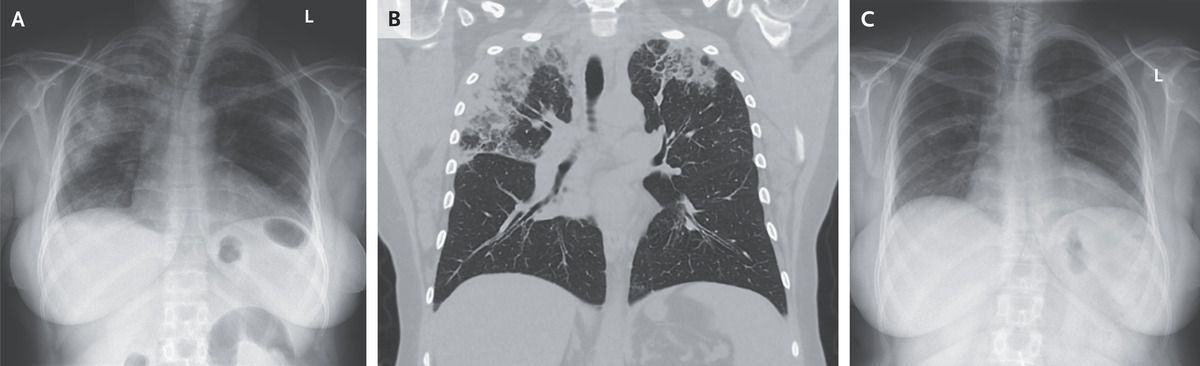

A 54-year-old woman with asthma and allergic rhinitis presented to the emergency department with a 3-month history of productive cough and dyspnea. She also reported fevers, chills, night sweats, and an unintentional 9-kg (20-lb) weight loss. Her medications were montelukast, cetirizine, and an albuterol inhaler. She was a lifelong nonsmoker and had not traveled recently. On lung examination, there was expiratory wheezing and diffuse crackles. Laboratory testing showed an absolute eosinophil count of 5240 per cubic millimeter (reference range, 40 to 360). A chest radiograph showed peripheral airspace opacities on both sides (Panel A). Subsequent computed tomography of the chest showed upper lobe–predominant peripheral and subpleural consolidations that spared the perihilar region (Panel B). The radiographic pattern was described as a “photographic negative of pulmonary edema” — a finding suggestive of chronic eosinophilic pneumonia. Serum testing for IgE against Aspergillus fumigatus, antibodies against coccidioides, and antineutrophil cytoplasmic antibodies was negative. Bronchoscopy with bronchoalveolar lavage was notable for 74% eosinophils in the cell count (reference value, <2) and negative tests for infectious diseases. A diagnosis of chronic eosinophilic pneumonia was made. Treatment with oral prednisone was started. At follow-up 17 days later, the patient’s symptoms had abated and the radiographic findings had resolved (Panel C). The patient continued to take prednisone for 5 months and had no further flare-ups.